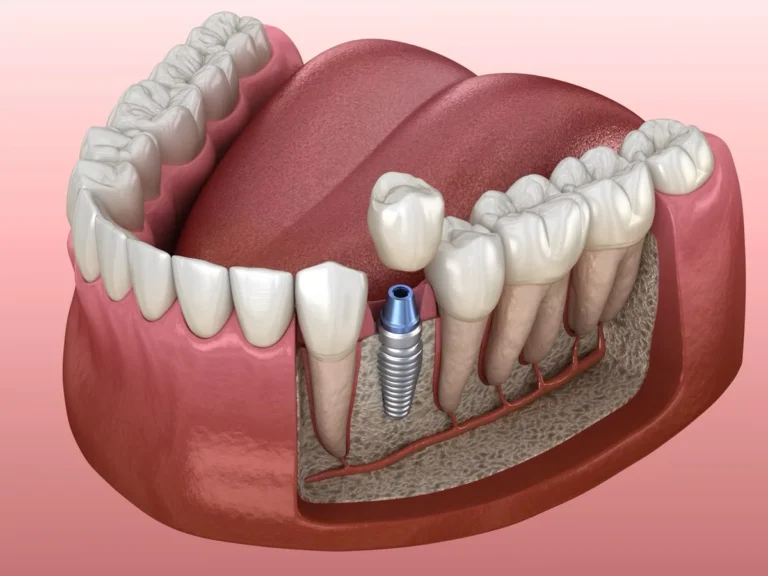

3 BENEFÍCIOS DOS IMPLANTES FEITOS AQUI

Uma equipe multidisciplinar planeja e executa o procedimento, garantindo diagnóstico preciso e o tratamento ideal para seu sorriso. Conheça as etapas.

1. Estabilidade Funcional

Implantes fornecem suporte firme para mastigação eficiente, evitando soluções frágeis como próteses móveis.

2. Preservação Óssea

Afixação direta ao osso reduz perda óssea progressiva e mantém a estrutura facial.

3. Durabilidade elevada

Materiais resistentes oferecem longa vida útil, diminuindo retrabalhos e custos futuros.

O que é um Implante Dentário?

Implante dentário é uma raiz dental artificial instalada no osso maxilar, pelo Implantodontista. Contudo a cirurgia é pouco invasiva, e repõe melhor um dente perdido, ou até a arcada completa.

A Implantodontia permite portanto realizar melhores tratamentos para colocar um dente ou vários dentes, bem como para a arcada completa em um implante total com carga imediata para a reabilitação oral de todos os dentes.

Na Ferst Odontologia, os implantes dentários são realizados com planejamento cuidadoso e tecnologia moderna para devolver a função e a estética do sorriso. Os implantes substituem dentes perdidos de forma segura e eficiente, proporcionando mais conforto, firmeza na mastigação e um resultado natural.